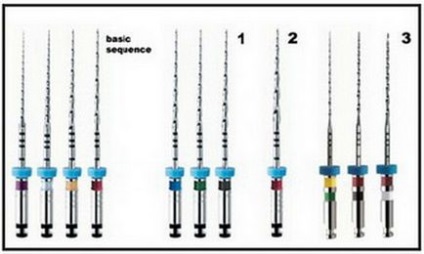

Endodontic eszközök Mtwo (VDW, München, Németország) - a közelmúltban bemutatott a piacra az új generációs nikkel-titán eszközök. A szabványos ez a rendszer magában foglalja a négy fő szerszám csúcsa mérete változik # 10 és # 25 és kúpos 0,04-0,06 (# 10 megfelel a kúpossága .04, # 15-0,05 kúpos, # 20 - # kúpos .06 és 25-0,06 kúpos).

Ábra. 1. Eszközök Mtwo, alapkészlet és kiegészítő fájlok feldolgozásához csúcsa.

Tipikus szekvenciát Mtwo rendszer tartalmaz négy szerszámot, hogy alkalmazzák a kisebb átmérőjű és kúpos, hogy nagyobb a következő sorrendben: 10 / .04, 15 / .05, 20 / .06, 25 / .06.